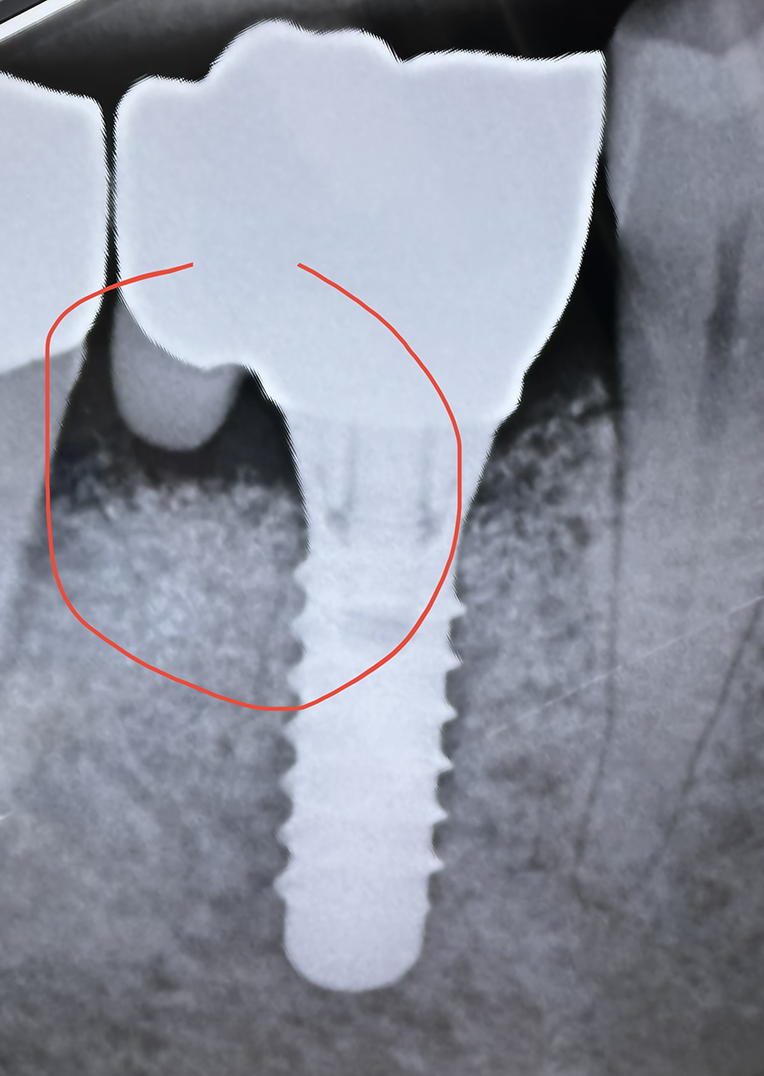

Neues Design bei Implantatkronen schützt besser vor Periimplantitis

(Parodontose bei Zahnimplantaten)

Forscher und Zahnmediziner haben ein neues Design für Implantatkronen entwickelt, das das Risiko von Periimplantitis, einer häufigen Komplikation nach der Platzierung von Zahnimplantaten, signifikant reduzieren könnte.

Periimplantitis ist eine entzündliche Erkrankung, die den Knochen um ein Zahnimplantat herum betrifft und zum Implantatverlust führen kann. Die Infektion wird oft durch Bakterien verursacht, die sich in den Spalten zwischen dem Implantat und der darüberliegenden Krone ansammeln.

Das neue Design nutzt eine innovative Methode, um die Bildung dieser bakteriellen Biofilme zu minimieren. Es beinhaltet eine verbesserte Passform zwischen Implantat und Krone, um weniger Platz für Bakterien zu bieten, und verwendet Materialien mit antibakteriellen Eigenschaften.

Darüber hinaus kann das neue Design den Zugang für die Reinigung und Pflege des Implantats verbessern, was ein weiterer Schlüssel zur Vermeidung von Periimplantitis ist. Die Forscher betonen, dass eine gute Mundhygiene nach wie vor von entscheidender Bedeutung ist, um die Gesundheit der Implantate zu gewährleisten, auch mit dem neuen Design.

Die ersten Tests mit diesem neuen Design haben vielversprechende Ergebnisse gezeigt. In klinischen Studien zeigte sich eine signifikante Reduktion der Bakterienansammlungen und eine verbesserte Gesundheit des umgebenden Gewebes.

Diese spannende Neuentwicklung wurde in der ABA Aeschenplatz Zahnklinik und der ACC Am Claraplatz Zahnklinik eingeführt, wo sie vom engagierten Zahnärzteteam unter der Leitung von Dr. D. Marschall implementiert wird.

Es wird erwartet, dass diese Innovation die Lebensdauer von Zahnimplantaten verlängert und die Notwendigkeit von Revisionseingriffen und Implantatwechseln reduziert. Die Forscher sind jedoch vorsichtig und betonen, dass weitere Studien erforderlich sind, um die langfristige Wirksamkeit des Designs und seine möglichen Auswirkungen auf die Gesamtgesundheit des Patienten zu beurteilen.

Das neue Design ist ein aufregender Schritt vorwärts in der Zahnmedizin und könnte dazu beitragen, die Lebensqualität für Millionen von Menschen zu verbessern, die Zahnimplantate tragen. Der Fokus auf die Verbesserung der Implantatgesundheit zeigt, dass die Medizin weiterhin Wege findet, um die Patientenversorgung zu verbessern.

Dr. Marschall und sein Team sind bekannt für ihre Expertise in der Implantologie und haben bereits in der Vergangenheit signifikante Beiträge zur Verbesserung der Zahnimplantat-Technologie und -Verfahren geleistet. Diese neueste Entwicklung steht im Einklang mit ihrem fortgesetzten Engagement für exzellente Patientenversorgung und höchste medizinische Standards.

Die beiden Kliniken sind bekannt für ihre hochmoderne Ausstattung und ihr Engagement für kontinuierliche Forschung und Entwicklung. Mit dieser neuen Technologie stärken sie ihren Stand als führende Einrichtungen in der Implantologie.

Das neue Implantatkronen-Design ist bereits in der klinischen Anwendung und zeigt vielversprechende Ergebnisse.

Neues Design bei Implantatkronen

Periimplantitis betrifft den Knochen, um den Zahnimplantat herum.